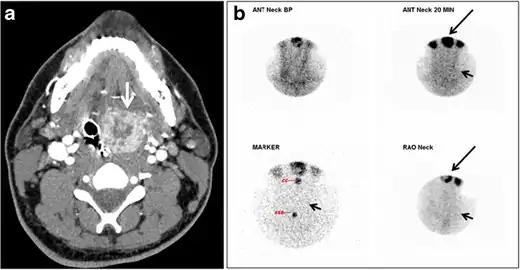

Fig. 17. Ectopic thyroid on the left parotid gland with a palpable left parotid mass in a 69-year-old male patient. a, b Axial and coronal enhanced neck CT scan demonstrates well-defined homogeneous enhancing mass (white arrows) within the left parotid gland with preserved surrounding fat planes. It also shows a normal thyroid in normal position in the lower neck. c Image taken 20 minutes after 5 mCi injected Tc99m-Pertechnetate shows normal thyroid uptake of tracer and physiological uptake in the salivary glands (short black arrow). There is a distinct focus of abnormal tracer accumulation in the left parotid/submandibular region. Patient was given lemon juice with evident normal washout from the salivary glands and relative retention by this abnormal focus (long black arrow).[1]